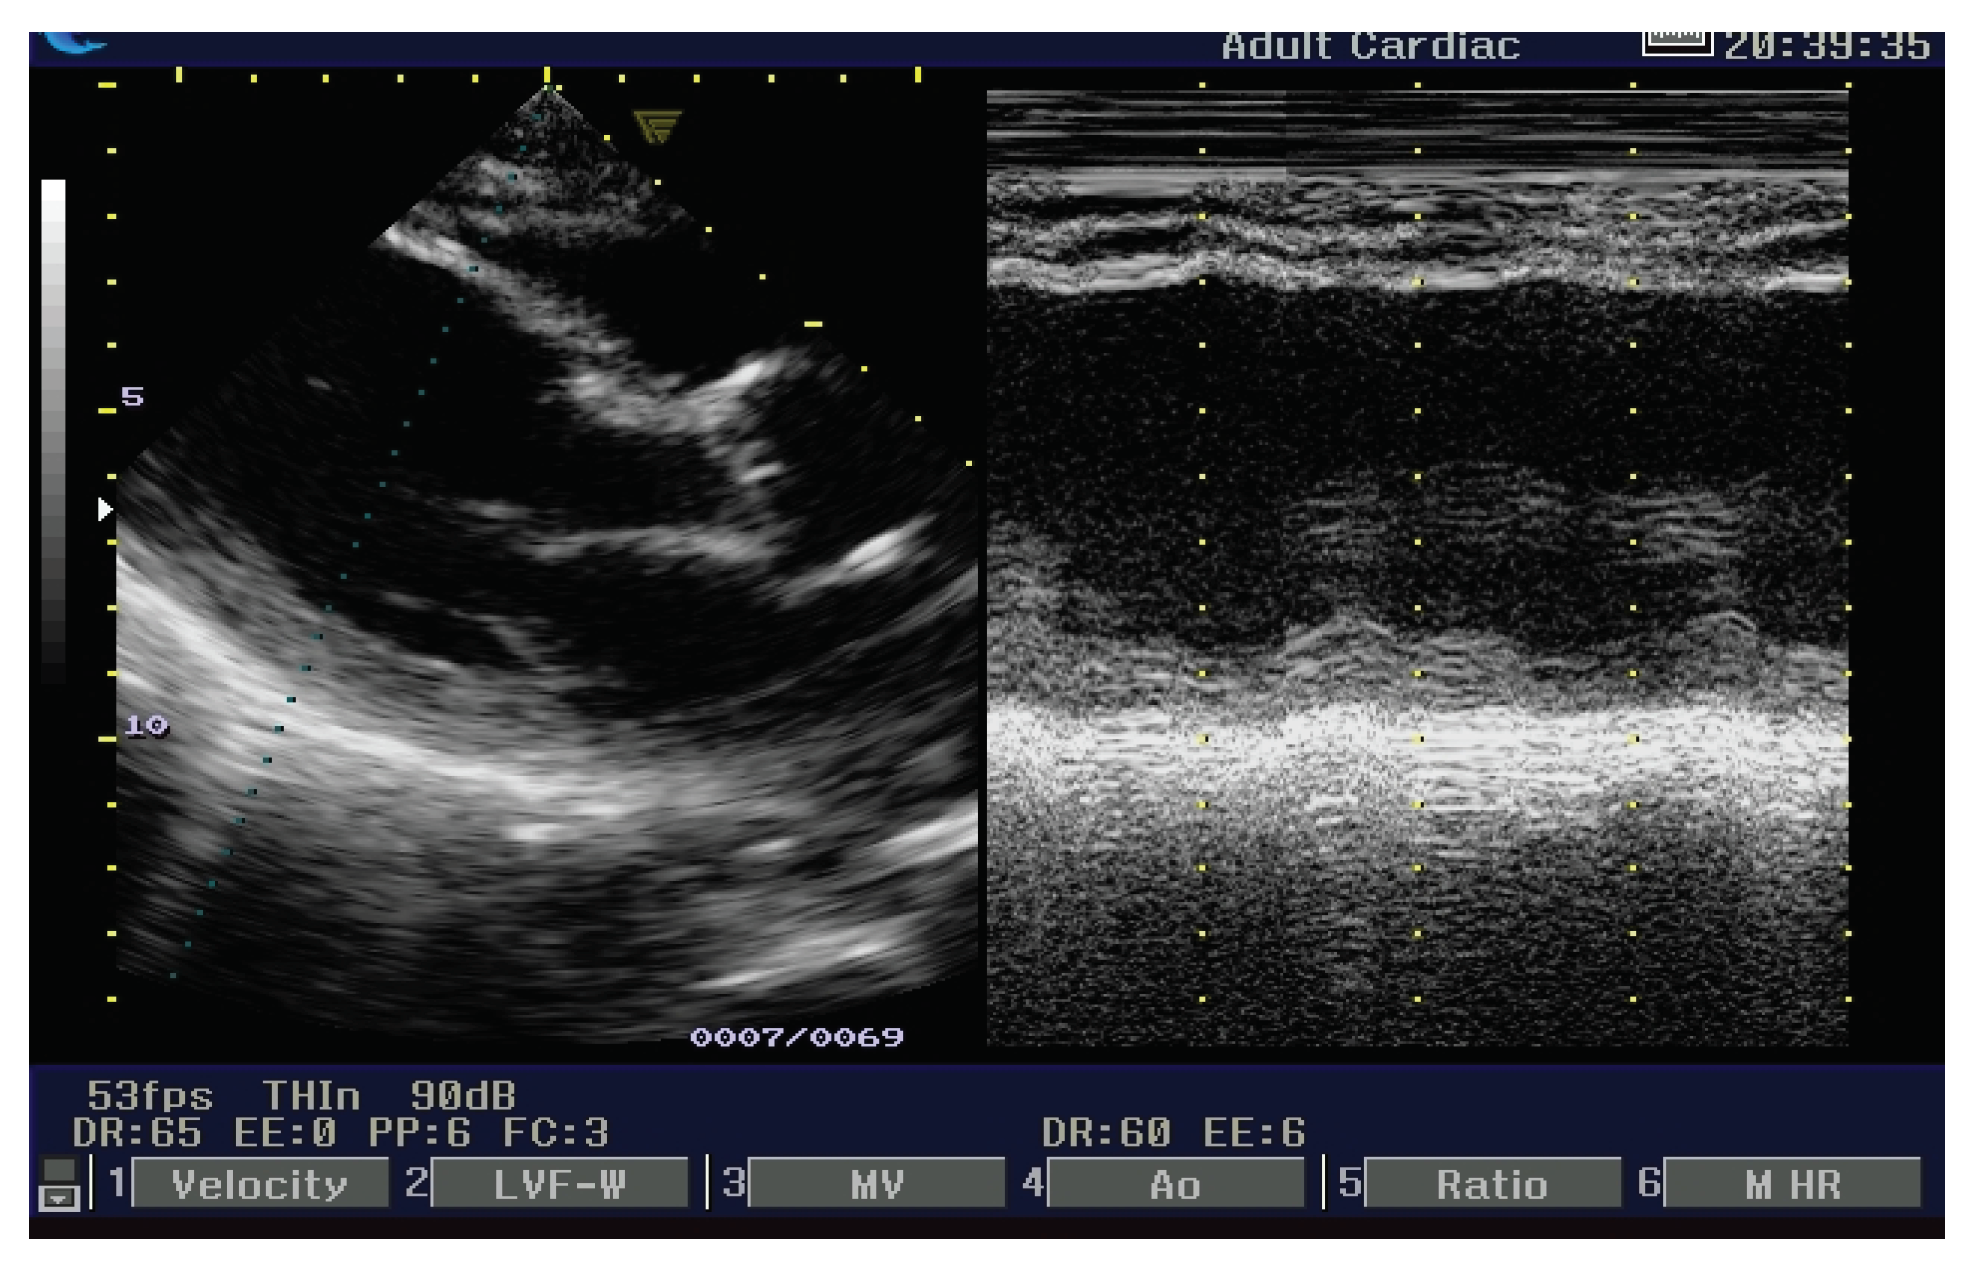

3.2.2. Echocardiogram